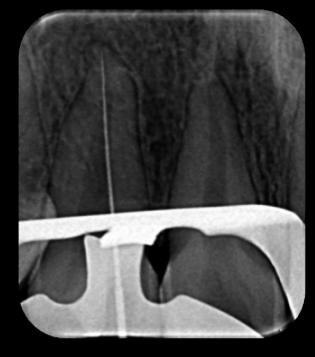

FASE DE ENDODONCIA

Se administró anestésico local de Lidocaína al 2% con epinefrina 1 en 80mil partes de millón, con la técnica infiltrativa supra perióstica con cierre de circuito por palatino. Para el acceso se tuvo en cuenta la forma, dirección y el tamaño de la cámara pulpar observada en la radiografía inicial; se accedió al conducto por palatino con fresa redonda de diamante mediana (0,18) (Fig. 3A y 3B). Se

realizó la extirpación del tejido vasculonervioso con tira nervios de distintos calibres, posteriormente fue realizada la conductometría una vez verificada esta, se realiza la preparación biomecánica con limas tipo

K de 25 mm desde la lima 15 hasta la 40, realizando irrigación copiosa con hipoclorito de sodio al 2.5 % (Fig. 3C, 3D, 3E y 3F).

Figura Nº3. A y B Acceso al conducto radicular por la cara palatina de la pieza con fresa de carburo. C y D Extirpación del paquete vasculonervioso. E y F Conductometría.

Fuente: Elaboración propia, septiembre 2021.